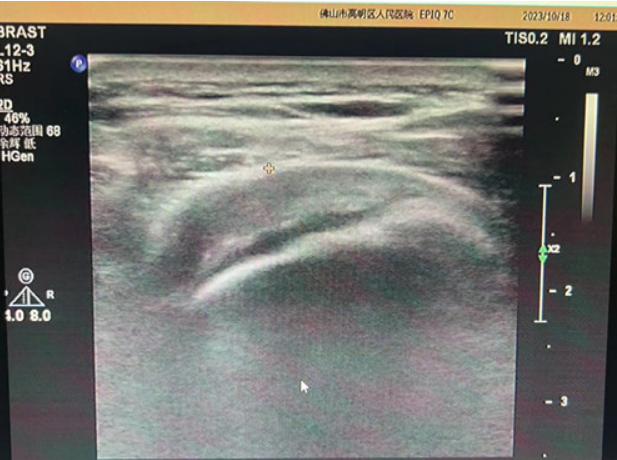

近半年来,我院康复医学科团队

为多位肩袖损伤的患者进行了

全面的康复治疗,

解决了患者的肩痛问题,

使患者关节功能及日常生活能力

得到很大改善。

患者情况